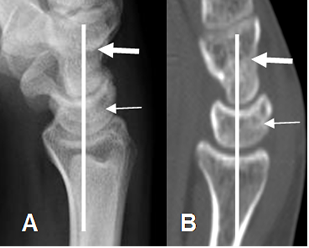

En la Rx lateral debe estar alineado el radio, con los huesos lunado y grande. (8). (Fig 11).

Fig 11. Alineación ósea.

A: Rx lateral y B: TAC reconstrucción lateral de muñeca.

Alineación entre los ejes del radio, huesos semilunar (Flecha delgada) y grande (Flecha gruesa).